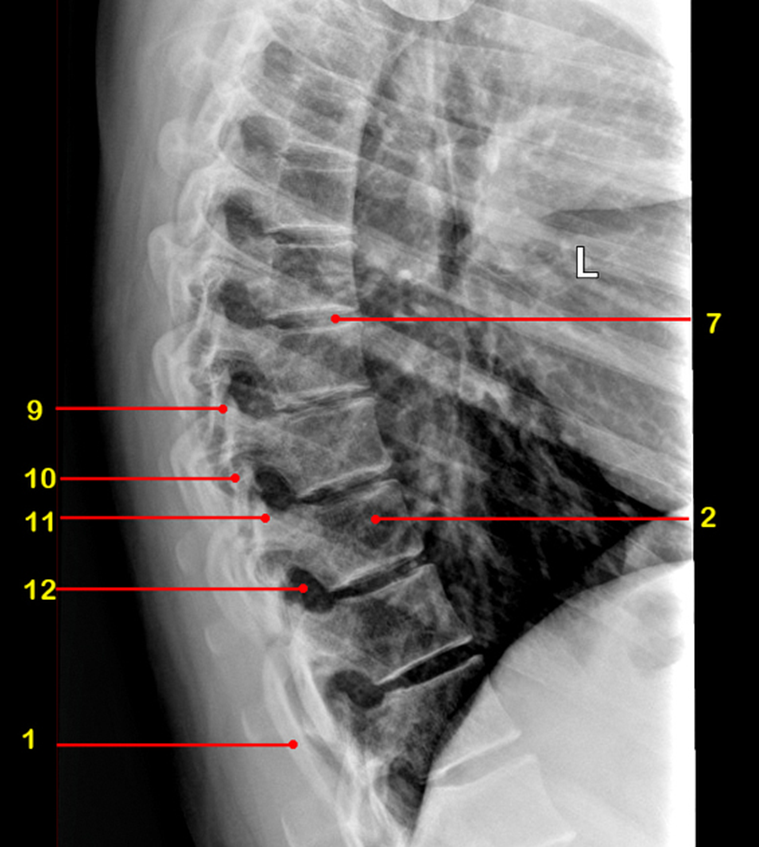

What view is this

sagittal

sagittal MRI